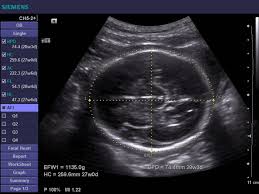

BPD – Biparietal diameter

Mula diukur pada minggu ke 13.

Saiz diantara 2.4-9.5 cm

Penanda, mesti nampak

i) a midline falx,

ii) the thalami symmetrically positioned

on either side of the falx,

iii) visualization of the Septum Pellucidum at

one third the frontooccipital distanc

4. HC – Head Circumferences

Diukur luar ke luar